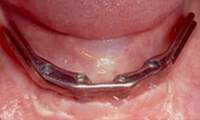

여러 개의 임플란트를 심은 뒤,

그 사이를 금속 막대로 연결해 튼튼한 지지대를 만들고,

그 위에 틀니를 안정적으로 고정하는 방식입니다.